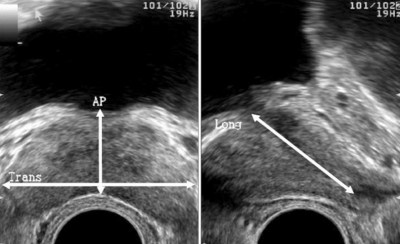

Lo que calculamos con la ayuda de la ecografía es el volumen prostático, y para ello se realiza la toma de medidas longitudinal, antero posterior y transversal.

Al lado izquierdo se aprecia una vista «superior» de la prostata, y al lado derecho una vista lateral de la misma. La vista superior o «desde arriba» permite medir los diámetros mayores antero posterior y transversal. La vista lateral permite tomar la medida de la longitud de la próstata (céfalo caudal).